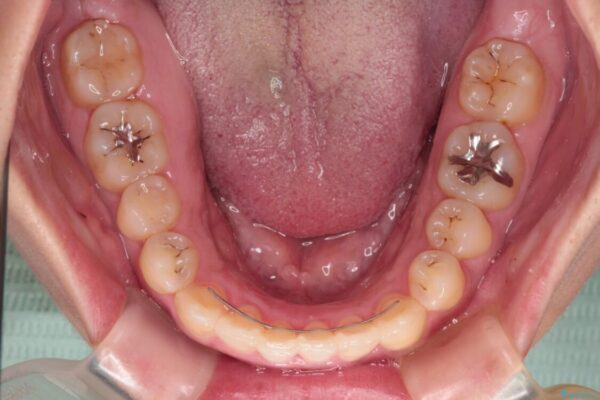

治療途中

• 【モニター】カリエール・ディスタライザーを併用した八重歯のインビザライン矯正 治療途中画像